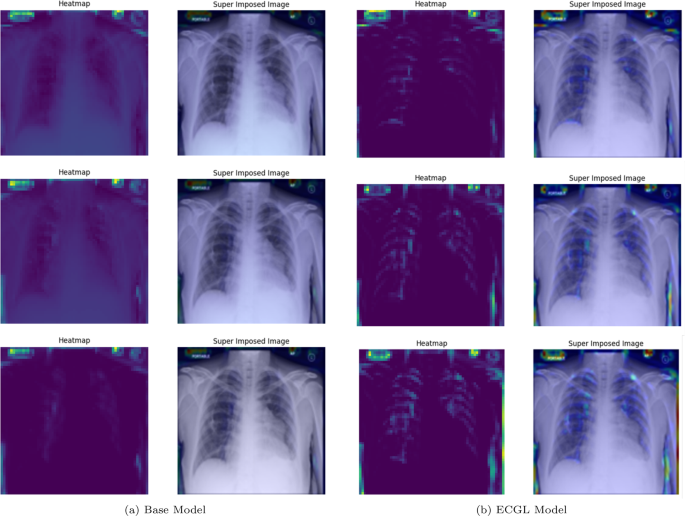

Likewise, Figs. 6 and 7 compare the proposed ECGL model and the Base model in terms of explainability by using GradCAM heatmaps. While both models generally seem to be focusing on similar areas (central region) of the chest X-rays, the color intensity in the heatmaps and superimposed images obtained from the ECGL model clearly shows a greater emphasis on certain regions that are related to the respiratory system and pneumonia disease. As it can be seen in Fig. 4(a) and 4(b) (correctly labeled instances), the highlighted regions of the Base model are more blurred, hazy, and spread out across the image, suggesting that the model’s decisions are less interpretable and apparent to the experts. Whereas the proposed ECGL model presents more focused and localized highlighted regions, showing that the model is primarily relying on specific areas of the image, relating to the particular region attacked by the disease, to make its prediction. The ECGL model makes it easier to understand the model’s reasoning and therefore presents more explainability. In addition, the ECGL model produces a more concentrated heatmap, indicating more confidence in prediction.

GradCAM Heatmaps (left column) and Superimposed images (right column) of the (a) Base model and (b) ECGL model for correctly labeled instances. The illustrated heatmaps correspond to GradCAM visualizations for labels 0 (normal), 1 (pneumonia present), and 2 (pneumonia absent, abnormalities exist), arranged from top to bottom, respectively

GradCAM Heatmaps (left column) and Superimposed images (right column) of the (a) Base model and (b) ECGL model for incorrectly labeled instances. The illustrated heatmaps correspond to GradCAM visualizations for labels 0 (normal), 1 (pneumonia present), and 2 (pneumonia absent, abnormalities exist), arranged from top to bottom, respectively